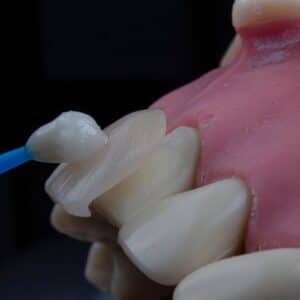

Photo Dental crown

What Are the Potential Costs Associated with Obtaining Temporary Restorations During the Dental Implant Process?

When you embark on the journey of dental implants, you may find yourself navigating a complex landscape of procedures and options. One crucial aspect of this process is the use…